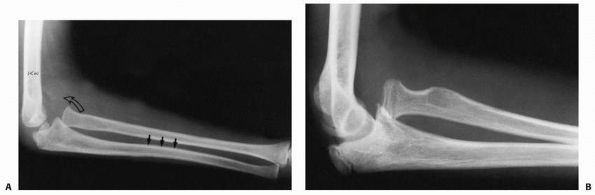

![]() |

FIGURE 12-37 Ulnar bow line. A. The injury film of an 8-year-old girl who fell, spraining her arm. Note anterior bow of the ulna (black arrows) and loss of the radiocapitellar relation (open arrow). B. Film at time of diagnosis. Note the persistent ulnar bow and overgrowth of radius.

The shape of the ulna in patients with a seemingly isolated dislocation

dislocation (see Figs. 12-3 and 12-37).77,84,118,128